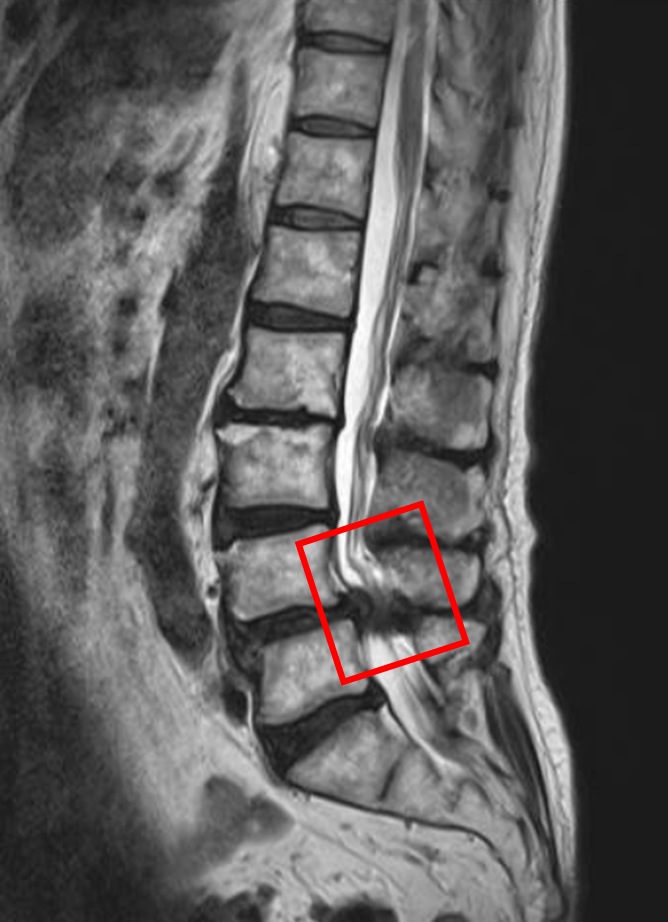

この患者様は赤い枠で示されている箇所(L4/5)に脊柱管狭窄症を認めます。